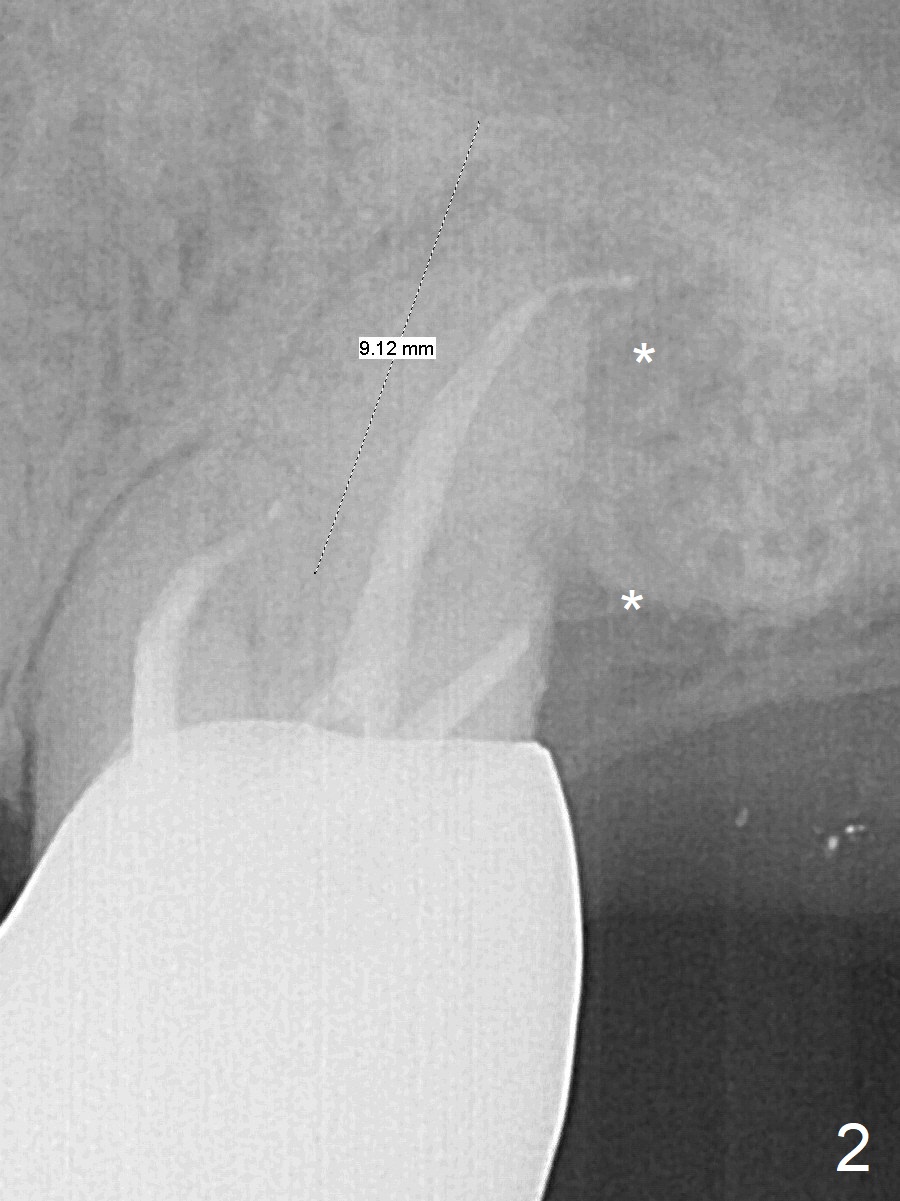

A 53-year-old man cannot chew on the left side with distal abscess in spite of RCT for #14 (* in Fig.1,2 (taken 11 ad 21 months postop, respectively)). After extraction (Fig.3 (CBCT coronal section) black area), start osteotomy with 2 mm drill (red outline) in the septum buccal to the palatal (P) socket). Following 2 mm drill removal (Fig.4), use 4.3 mm Magic Drill (red outline) for ~ 9 mm. When the osteotomy is being done, the osteotomy most likely shifts palatal (Fig.5 arrow) because of thin bone palatally. When the MD is removed (Fig.6), use Magic Sinus Lifter (Fig.7 pink) for sinus lift (arrow). The implant is to be 5x11 mm or larger. Because of the distal defect (Fig.1,2), start osteotomy mesially. Take Alginate impression before surgery for possible orthodontic treatment. Since bone density is high, use higher voltage and longer time for X-ray.